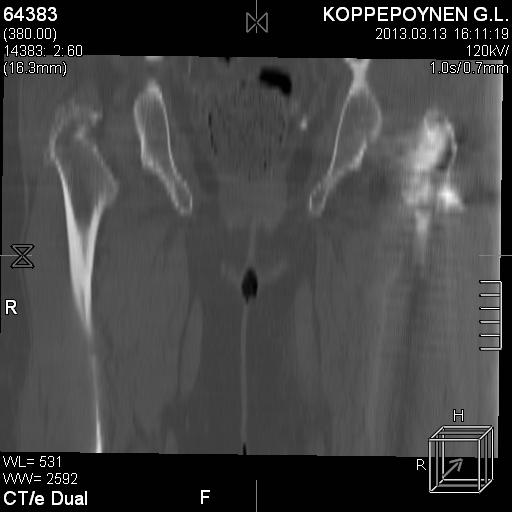

Делали КТ после операции.

|

Отправитель: Alexander Chelnokov 14 Октябрь 2013, 03:21

Непонятно, на какой вопрос с помощью КТ хотели получить ответ? IMHO это было ненужное исследование, все проблемы были видны на обычном снимке. А что на второй проекции? Где аксиальная или профиль?

есть КТ после операции. у пациентки направление введения стержня совпадает с направлением большого вертела, однако большой вертел расколот на 2 отломка. Задний отломок лежит по оси, передний отломом "отошел" и создается впечатление неправильного введения стержня. Динамизации у пациентки не было... Привезут снимки после операции, скину